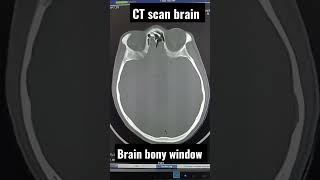

CT scan brain bony window #radiologist #radiology #ctscan

CT scan brain bony window #radiologist #radiology #ctscan #Ctscan #Mri #Xray CT Scan || 3D Whole Abdomen || #Liver #Kidney #Stomach #Heart #Shorts

CT scan brain bony window #radiologist #radiology #ctscan

CT scan brain bony window #radiologist #radiology #ctscan #Ctscan #Mri #Xray CT Scan || 3D Whole Abdomen || #Liver #Kidney #Stomach #Heart #Shorts